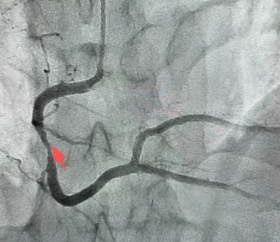

检查后发现,他腹黑的前降支血管里,早就长出了易损斑块,斑块依然闹翻,酿成的大面积血栓把血管都备堵死了。